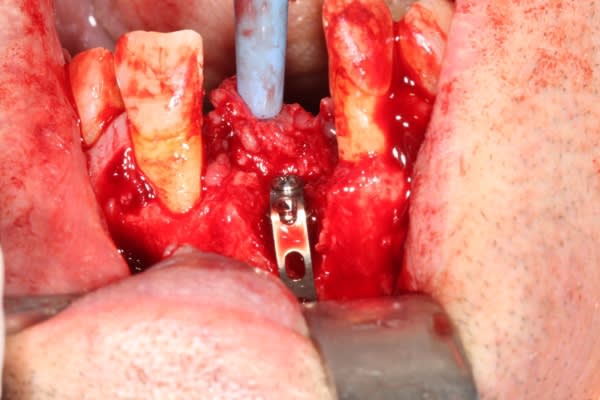

Extraction implantation immédiate mais il y a au moins 7 spires à nue... (photo 1, 2)

dans cette technique un pilier de 2mm de haut est vissé sur l'implant, ce pilier contient un orifice qui permet de transfixer la barre (photo 3,4)

l'espace créé est rempli avec un biomat et le tout est recouvert d'une membrane